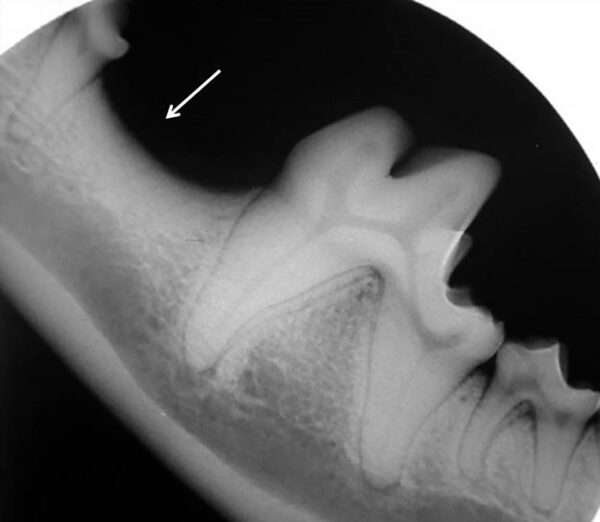

- La superposición del orificio mentoniano sobre la porción apical de la raíz en el canino mandibular de un perro produce una apariencia similar a la zona radiolúcida que aparece cuando existe patología periapical.

- En el gato, el foramen mentoniano se encuentra en el espacio interdental entre el diente canino y el tercer premolar mandibular o a nivel de este último (imagen 5).

- Otra apariencia radiológica es el efecto chevron, que consiste en un área de radiolucidez, más frecuente en incisivos maxilares y dientes caninos en el perro, que radiológicamente se parece a lesiones de origen endodóntico. En este caso, la radiolucidez tiene una forma triangular y el espacio del ligamento periodontal no varía alrededor de la raíz (imagen 6).